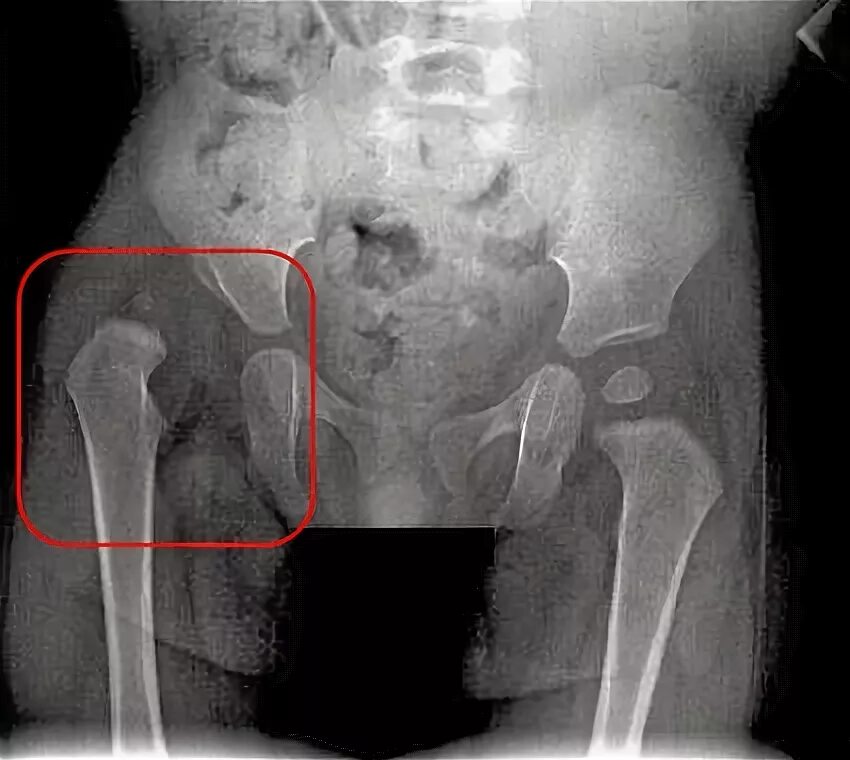

Тазобедренного сустава у детей